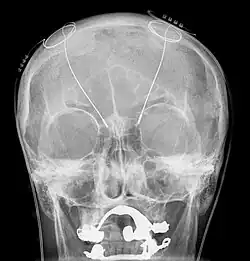

A radiography during an intervention of deep brain stimulation

Treatment of intention tremor is very difficult.[16] The tremor may disappear for a while after a treatment has been administered and then return. This situation is addressed with a different treatment. First, individuals are asked if they use any of the drugs known to cause tremors. If so, they are asked to stop taking the medication, and then are evaluated after some time to determine if the medication was related to the onset of the tremor. If the tremor persists, treatment that follows may include drug therapy, lifestyle changes, and more invasive forms of treatment, including surgery such as and thalamic deep brain stimulation.[14]

A more radical treatment that is used in individuals who do not respond to drug therapy, physical therapy, or any other treatment listed above, with moderate to severe intention tremors, is surgical intervention. Deep brain stimulation and surgical lesioning of the thalamic nuclei has been found to be an effective long-term treatment with intention tremors.

Deep brain stimulation treats intention tremors, but does not help related diseases or disorders such as dyssynergia and dysmetria.[17] Deep brain stimulation involves the implantation of a device called a neurostimulator, sometimes called a "brain pacemaker". It sends electrical impulses to specific parts of the brain, changing brain activity in a controlled manner. In the case of an intention tremor, the thalamic nuclear region is targeted for treatment. This form of treatment causes reversible changes and does not cause any permanent lesions. Since it is reversible, deep brain stimulation is considered fairly safe. Reduction in tremor amplitude is almost guaranteed and sometimes resolved. Some individuals have seen sustained benefits in MS progression.[18]